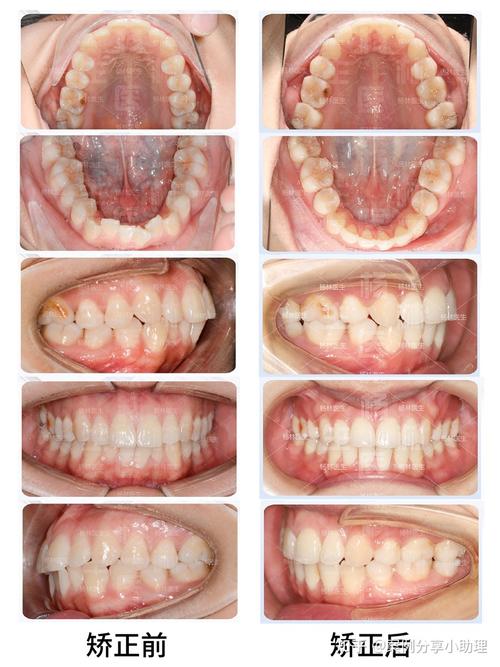

- 核心数量: 虽然列出了19种,但最常用、最核心的口内像组合是9张:上牙列咬合面、下牙列咬合面、上牙列右侧颊侧、上牙列左侧颊侧、下牙列右侧颊侧、下牙列左侧颊侧、上颌前牙区唇侧、下颌前牙区唇侧、正中咬合关系观,这9张基本能覆盖牙齿排列、形态、牙龈、咬合等核心信息。

- 定期拍摄: 在治疗开始前(T0)、治疗中(如每次复诊或关键阶段)、治疗结束后(T1)都需要拍摄完全相同角度和位置的照片,以便进行对比评估。